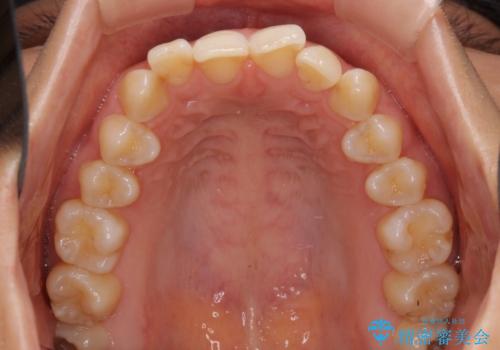

- 前歯の叢生と口元の閉じにくさを気にして来院された患者様です。

奥歯の咬み合わせを見ると、上顎が下顎に対して相対的に前方にありました。

口元の閉じにくさを改善するためには、上顎臼歯を後方に移動させた咬み合わせにする必要があります。

インビザライン単体で改善することも可能ですが、達成する可能性が高くないため、カリエールディスタライザーという補助装置を併用して、より確実性を上げることとしました。

奥歯の咬み合わせを改善しながら、並行してインビザラインで歯列を整えることとしました。

カリエールディスタライザーを併用したことで、確実かつ短期間で治療を終えることができました。